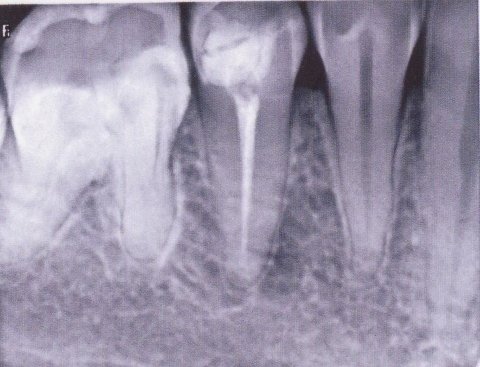

Примеры лечения радикулярных кист челюстей без скальпеля:

Фото: до лечения депофорезом

Фото: после лечения депофорезом